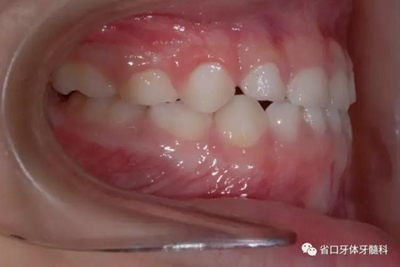

圖5 左側45度牙相

6.jpg

圖6 右側45度牙相